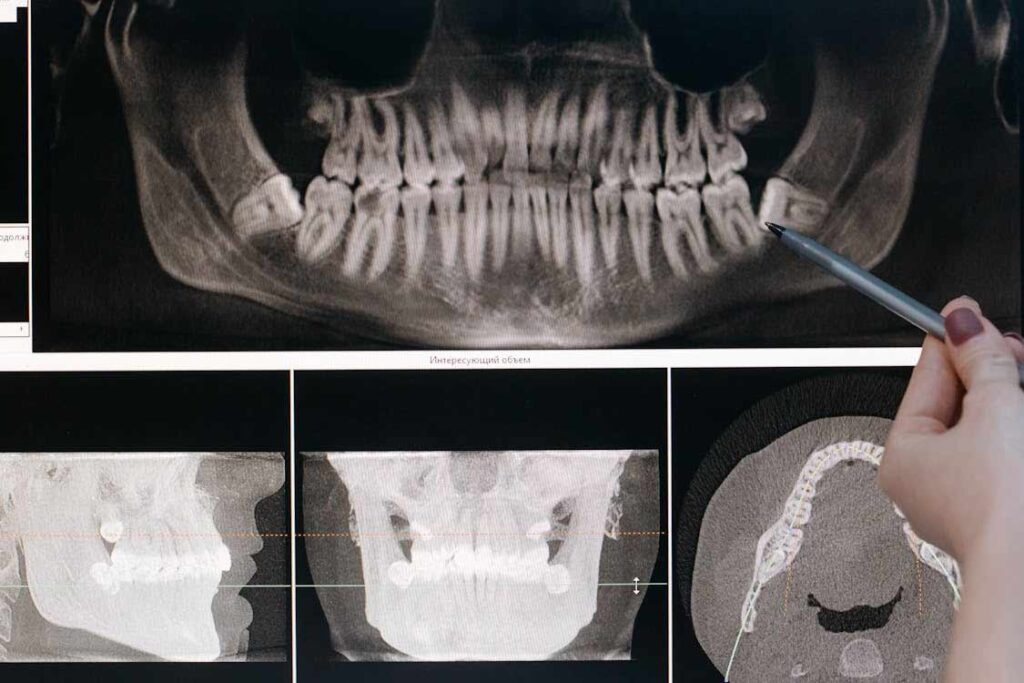

Though we can’t always see our wisdom teeth, they can cause us acute and unexpected pain due to decay or infection. They may remain fully or partially hidden beneath the gums due to a lack of space in the mouth.

Though they often remain below the gumline, wisdom teeth can partially grow outside your gums, leading to tooth decay. This can cause substantial pain if the decay infects the tooth or if the infection spreads to surrounding areas. If you are experiencing wisdom tooth pain, you should consult a dentist right away. Emergency Dental Care USA in Miramar, FL can treat any tooth infection you may have and, if needed, extract the tooth or teeth.